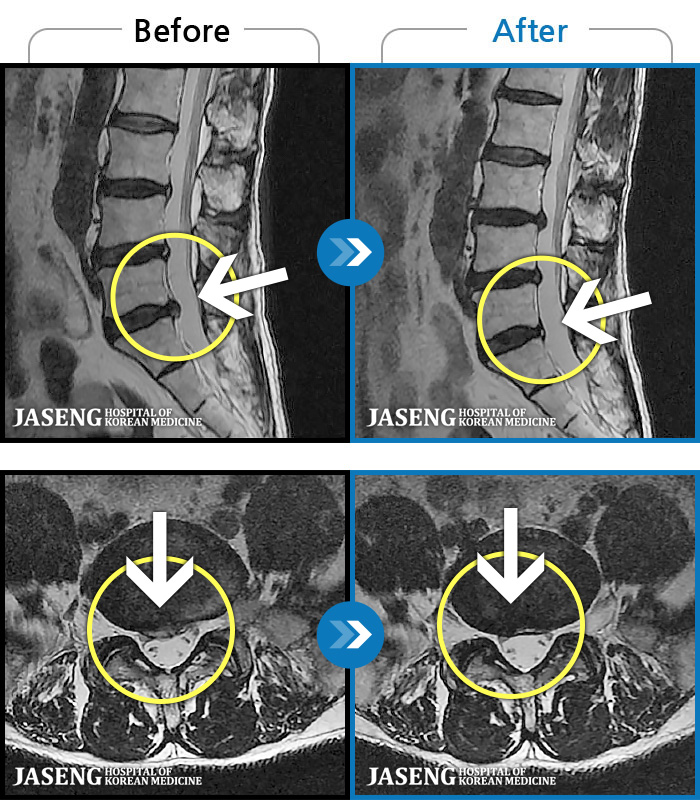

MRI ũ ʸ Ȯϼ.

ó ̾ ߰, ణ ٷϵ ݵǾ ϻȰ ¿ϴ. |